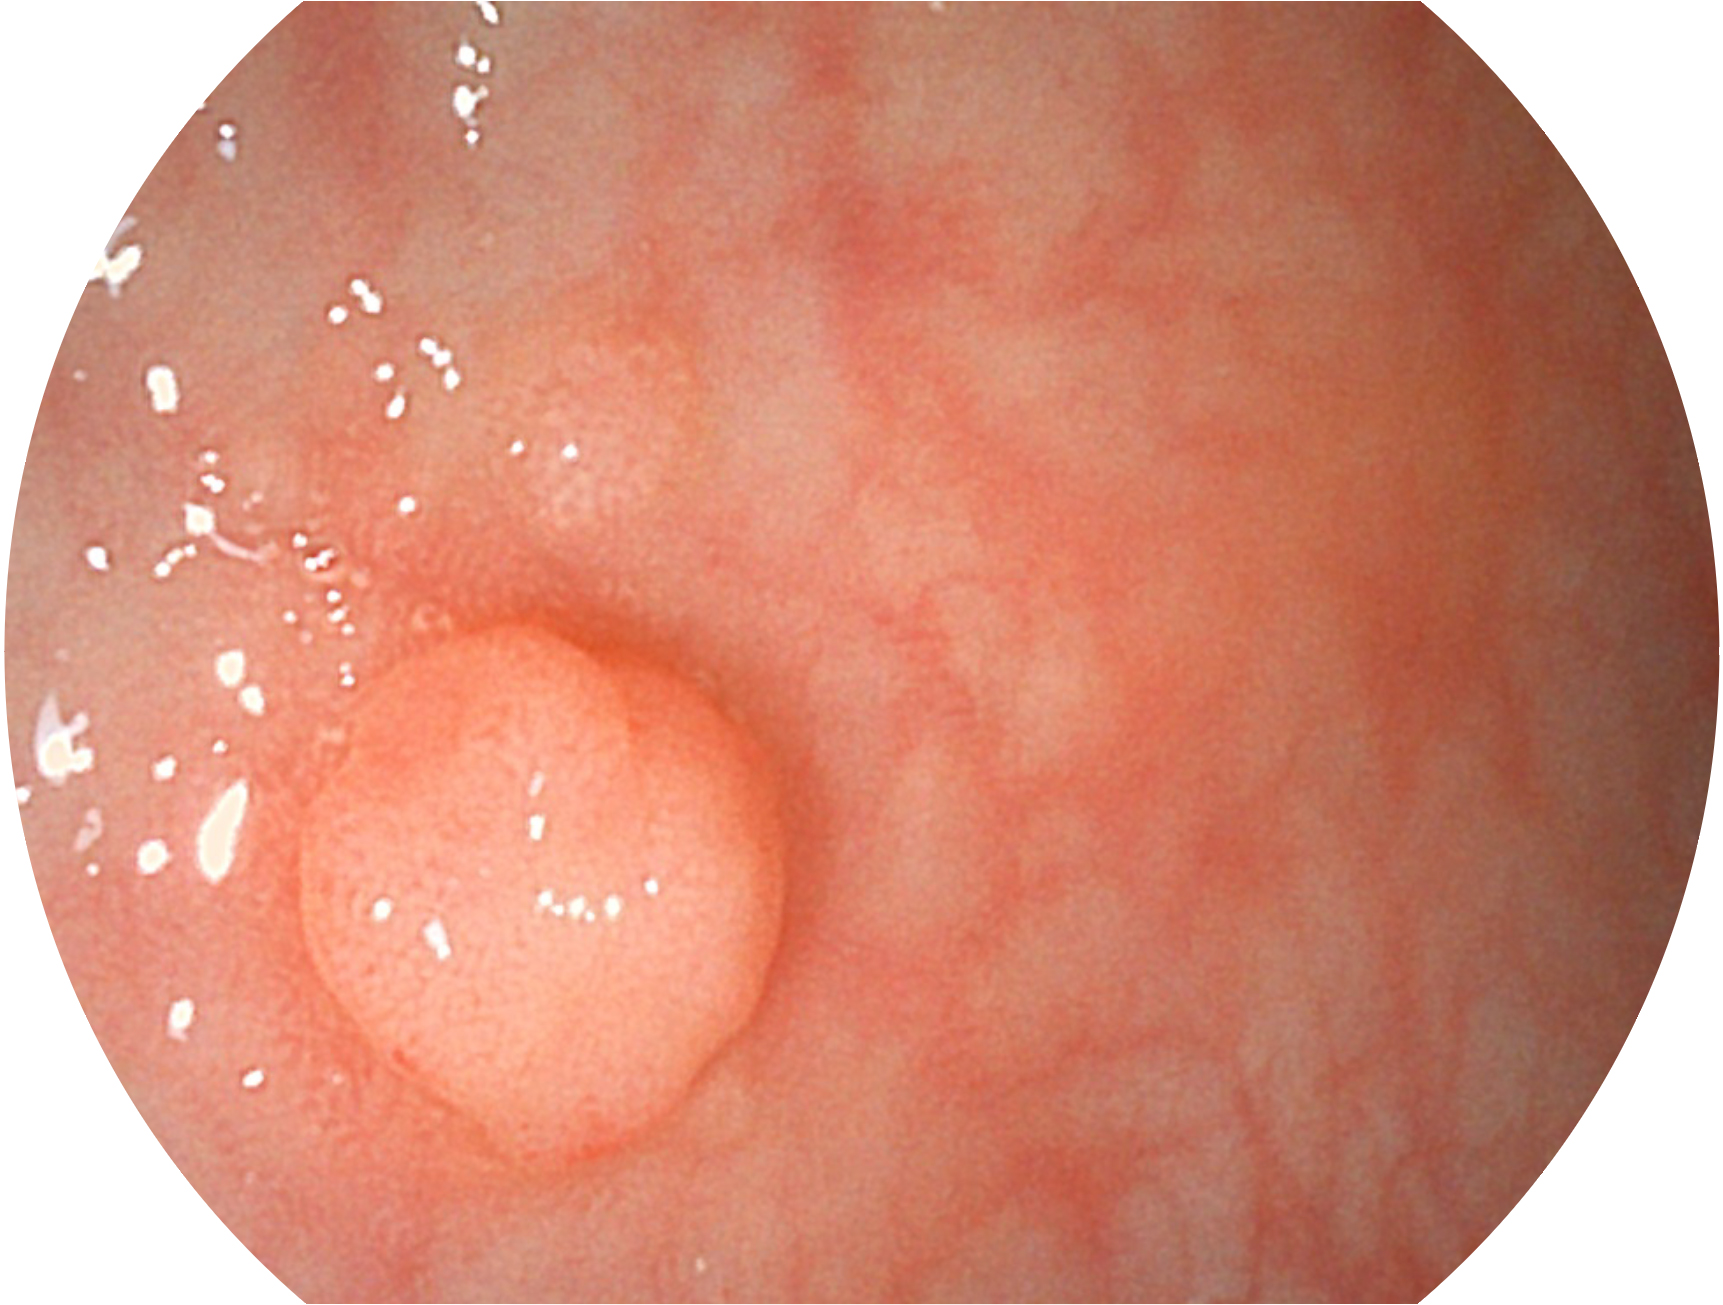

開立新開發(fā)的內(nèi)鏡染色技術(shù),主要是基于多波長(zhǎng)LED 光源的開發(fā),VLS-55Q 四波長(zhǎng)LED 光源是由四個(gè)不同顏色的LED光按照相應(yīng)照明模式所規(guī)定的特定發(fā)光比例進(jìn)行合束后形成,合束后形成的照明光的光譜由紅光、綠光、藍(lán)光及藍(lán)紫光這四個(gè)不同的波段范圍構(gòu)成。具有更高光譜自由度,通過(guò)光譜比例的控制,實(shí)現(xiàn)了聚譜成像技術(shù),英文全稱為“Spectral Focused Imaging, SFI”,縮寫為“SFI”和光電復(fù)合染色成像技術(shù),英文全稱為“Versatile Intelligent Staining Technology, VIST”,縮寫為“VIST”。